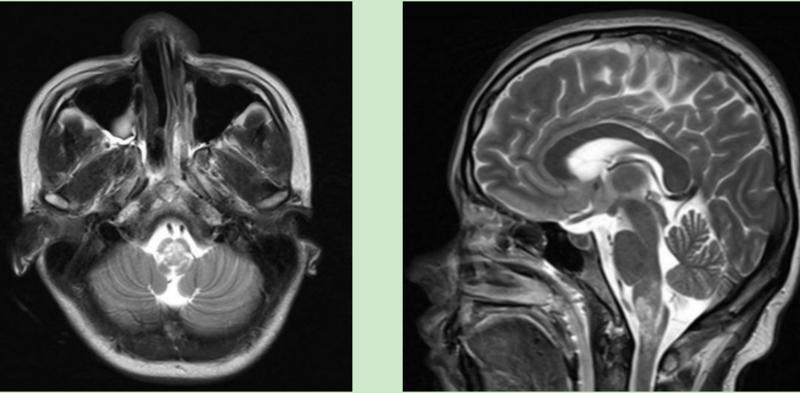

延髓病变,脑血管正常

然而,张女士入院时的磁共振提示:延髓病变。延髓是生命指挥中枢,虽然张女士生命挽救过来,但因延髓病变导致四肢瘫痪、呼吸肌无力,却使之一时无法脱离呼吸机。

广州市第一人民医院神经内科主任医师余健敏介绍,张女士转入NCU的第二天,确诊为视神经脊髓炎谱系疾病-极后区综合征。原来,为了尽快明确诊断病情,能够给予有效治疗,医务人员抽丝剥茧,迅速制定多项针对性措施。

炎症性?免疫性?代谢性?肿瘤性?鉴别诊断胶着了。仍然不能排除神经系统感染、神经免疫疾病、代谢性疾病。丰富临床经验的NCU医生迅速为病人完成腰椎穿刺术,脑脊液NGS结果阴性,结合脑电图感染性疾病基本排除。血清和脑脊液抗体提示AQP4(+)。最终曙光显现,在转入NCU第二天确诊,为视神经脊髓炎谱系疾病-极后区综合征。